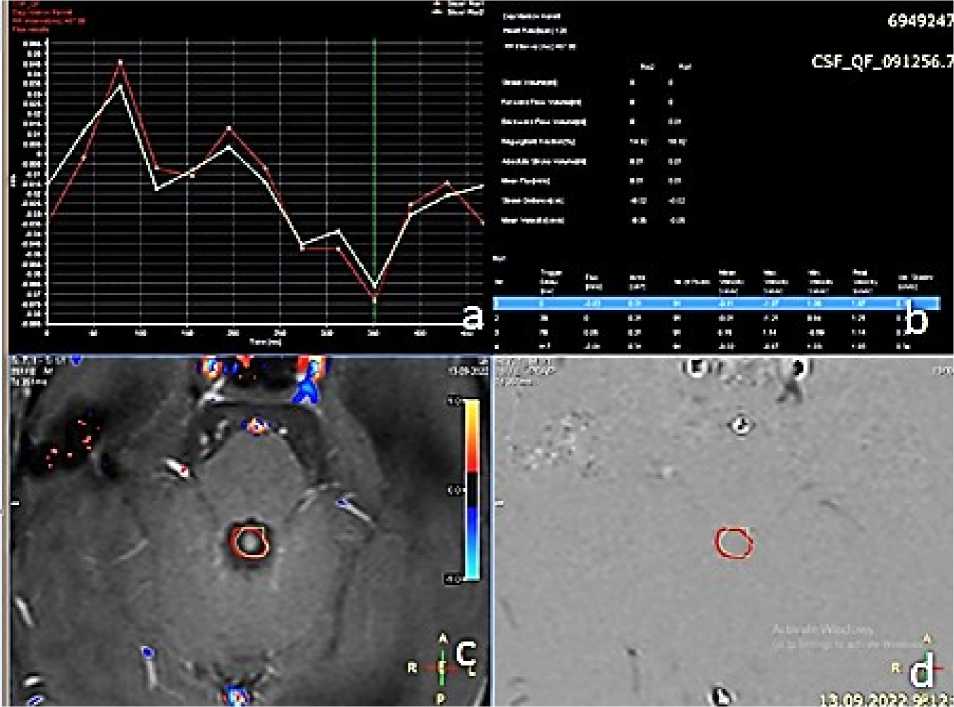

Оценка ликвородинамики проводилась с применением фазово-контрастной МРТ в режиме CSF_PCA, что позволяло объективно оценить наличие или отсутствие антеградного и ретроградного ликворотока (Рисунок 2).

Рисунок 2. Оценка ликвородинамики по данным фазово-контрастной МРТ (CSF_PCA): A — кривая ликворотока с отсутствием нисходящего потока; B — скоростные характеристики ликвора; C, D — проекция Сильвиева водопровода для оценки пассажа ликвора